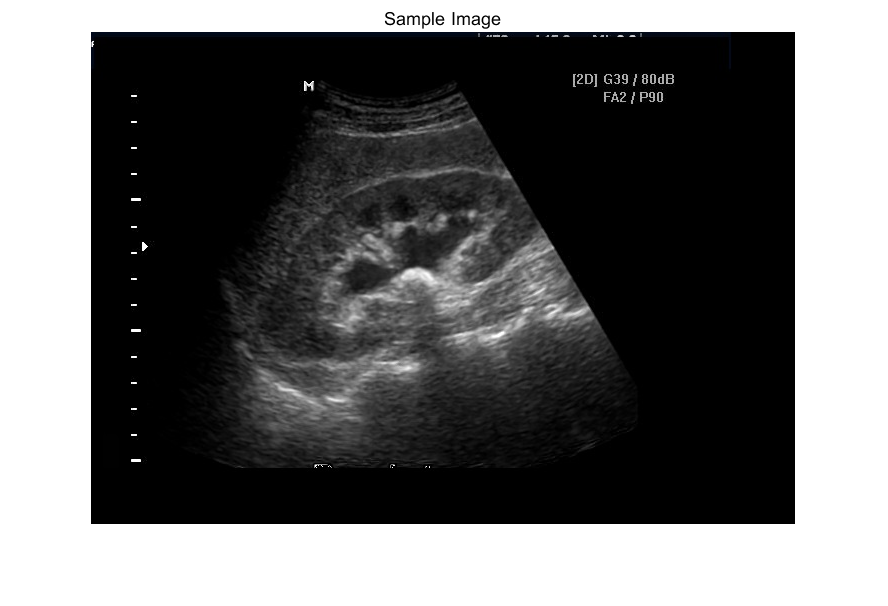

肾结石(Renal Calculi),又称肾石(Kidney Stone),是一种基于晶体形成的固体团块。在医疗操作中,精准定位尿路结石(Urinary Calculus)至关重要。由于超声图像中的斑点噪声(Speckle Noise)会给人工检测尿路结石带来困难,因此有必要采用自动化方法在超声图像中识别肾结石。

超声成像是用于诊断肾脏异常(Kidney Abnormalities)的影像学技术之一。肾脏结构与位置的改变、肢体水肿(Limb Edema)均属于肾脏异常的表现形式。此外,肾结石、肾囊肿(Cysts)、尿路梗阻(Obstructed Urine)、先天性畸形(Congenital Malformations)以及恶性细胞(Malignant Cells)增生等,也属于常见的肾脏疾病(Renal Problems)。通过采用合适的图像处理技术,可有效解决(超声图像中结石检测困难这一)问题。

imshow(original_image),title('Sample Image'); %a